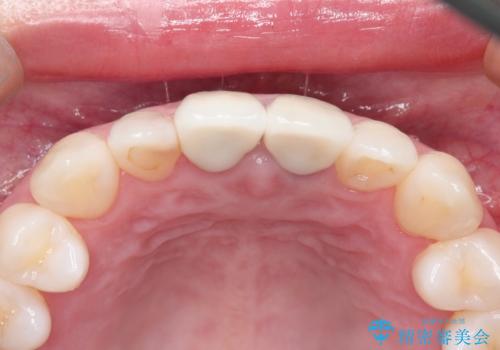

金属の土台をファイバーコアに交換後、オールセラミッククラウンを装着する計画としました。

かぶせ物と歯の境目の再設定を行い、適合の良いかぶせ物を装着することで、審美的に自然な状態に改善することができました。